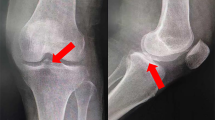

For fascial closure, either the barbed continuous suture using number #1–0 polydioxanone suture (Stratafix Symmetric PDS Plus, Ethicon) or the interrupted suture using number #2 triclosan-coated glycolide-lactide absorbable suture (Vicryl Plus Antibacterial suture, Ethicon) was used. The interrupted suture was used before October 2018, whereas the barbed suture was used after October 2018 (Fig. 1).

From the surgical record, the number of threads used and the closure type for fascia were addressed. Time for the start of anesthesia, skin incision, intraoperative radiograph, skin closure and exit from the operation room were also collected. Using these data, three different time intervals were calculated. “Closure time” was defined as the time from the intraoperative radiograph to the initiation of skin closure. In accordance with this definition, the closure time included insertion of real femoral component, irrigation, repair for capsule, muscle, and fascia, and closure for subcutaneous tissue. “Procedure duration” was defined as the time from the skin incision to the initiation of skin closure. “Total operation time” was defined as the time from the start of anesthesia to exit from the operation room (Fig. 1).